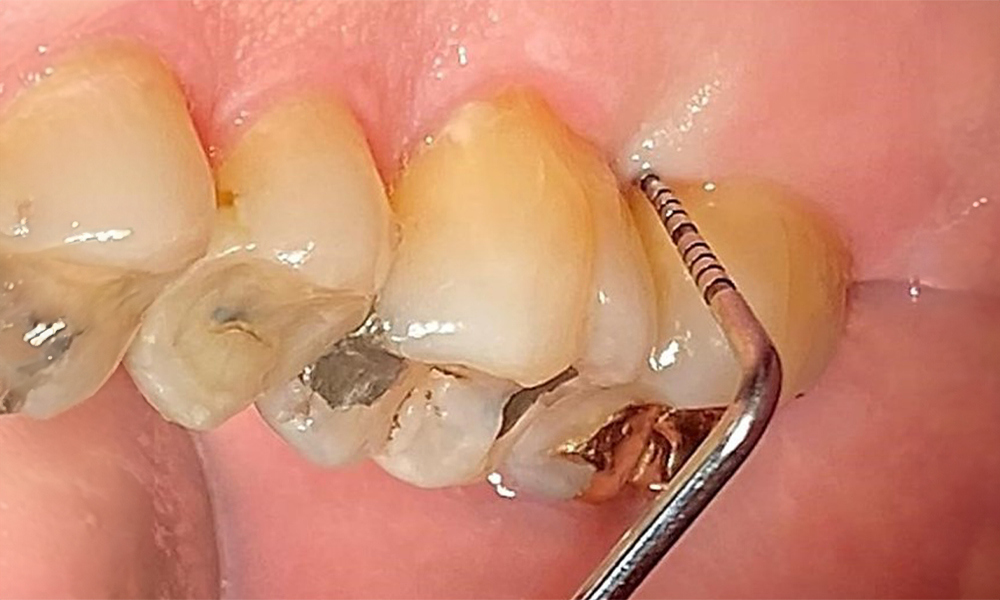

Dentaler Befund

Der Patient hat ein vollbezahntes Gebiss mit 28 Zähnen, an welchen sich im Molaren- und Prämolarenbereich Amalgamfüllungen und Compositefüllungen befinden. An Zahn 14 zeigt sich ein sichtbarer klinischer Randspalt. Zahn 27 hat ein suffizientes Goldinlay. Zudem zeigen sich generalisierte Attritionen und Abrasionen. (Abb. 2, Abb. 3, Abb. 4, Abb. 5, Abb. 6)

Parodontaler Befund

Der Patient hat eine Parodontitis Stadium II, Grad B (5). Die klinischen Sondierungstiefen liegen mit 1-3mm im physiologischen Bereich. Lokalisierte Sondierungstiefen finden sich an 17 und 27 jeweils mesiopalatinal mit 5mm. Es liegen generalisierte Rezessionen von 1-3mm vor mit partiellem Verlust der Interdentalpapillen (Abb. 2, Abb. 3, Abb. 4)